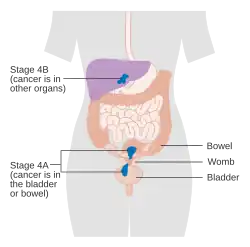

O carcinoma endometrial é estadiado cirurgicamente usando o sistema de estadiamento de cancro FIGO. O sistema de preparação do FIGO de 2009 é o seguinte:[56][57]

| Etapa | Descrição |

|---|---|

| I A | O tumor está confinado ao útero com menos da metade da invasão miometrial |

| IB | O tumor está confinado ao útero com mais da metade da invasão miometrial |

| II | O tumor envolve o útero e o estroma cervical |

| IIIA | O tumor invade a membrana serosa ou anexos |

| IIIB | Envolvimento vaginal e/ou parametrial |

| IIIC1 | Envolvimento do linfonodo pélvico |

| IIIC2 | Envolvimento de linfonodos para-aórticos, com ou sem envolvimento de linfonodos pélvicos |

| IVA | O tumor invade a mucosa da bexiga e/ou mucosa do intestino |

| IVB | Metástases distantes, incluindo metástases abdominais e/ou linfonodos inguinais |

A invasão miometrial e o envolvimento dos linfonodos pélvicos e para-aórticos são os padrões de disseminação observados com maior frequência.[2] Às vezes, é incluído um Estágio 0, neste caso denominado "carcinoma in situ".[9] Em 26% dos cancros presumivelmente em estágio inicial, o estadiamento intraoperatório revelou metástases pélvicas e à distância, tornando necessário um estadiamento cirúrgico abrangente.[25]

Cancro do endométrio em estágio III Cancro do endométrio em estágio IV

Cancro do endométrio em estágio IV